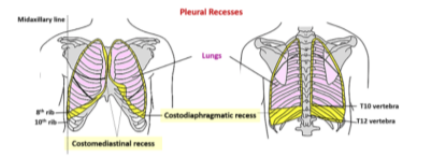

Pleural recesses

Two types of recesses —

The costodiaphragmatic recess

Also called costophrenic angles

Larger, located between the costal & diaphragmatic pleura of right & left pleural cavities

Occur at the costal reflection where the costal pleura becomes continuous with the diaphgramatic pleura

Deepest after broad expiration & shallowest after forced inspiration

The costomedisrinal recess

Smaller, anteriorly at the sternal reflection where the costal pleura is in contact with the mediastinal pleura

Larger on the left side due to cardiac notch of the left lung

Lungs don’t completely fill areas surrounded by pleural cavities — particularly anteriorly & inferiorly —

Costomediastinal recesses —

Occur anteriorly, particularly on the left side in relationship to the heart bulge

Costodiaphragmatic recesses —

Occur inferiorly between the lower lung margin & the lower margin of the pleural cavity